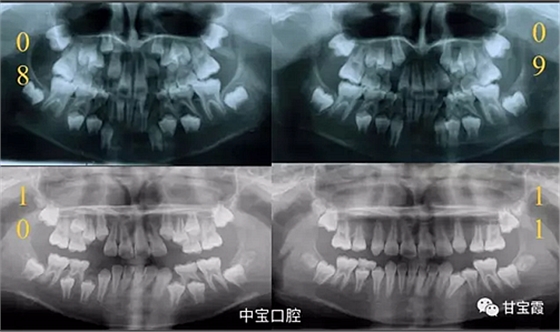

有一個(gè)七歲的小女孩,在替牙時(shí)媽媽發(fā)現(xiàn)孩子新長的牙不整齊,有一顆長到里面了,上下頜中線也不對稱,很著急就來到門診看牙。

經(jīng)過我臨床檢查和X線的診斷,決定早期干預(yù),每三個(gè)月定期復(fù)診檢查一次,并拔掉了幾個(gè)乳牙和四個(gè)恒牙,正畸專業(yè)叫序列拔牙。

經(jīng)過三年零九個(gè)月的看護(hù),最終戴上了固定矯治器,但是大家不難發(fā)現(xiàn),孩子的牙齒已經(jīng)排齊,上下中線也基本對齊,面型也好看多了,這樣矯正就變得簡單,療程自然縮短,孩子也不遭罪了。

這個(gè)故事告訴我們,只有家長早點(diǎn)把孩子帶給正畸醫(yī)生檢查,才能早期發(fā)現(xiàn)早期治療。起到了事半功倍的效果。矯正以后還不容易復(fù)發(fā),因?yàn)閺?8年的初診到11年戴矯正器這三年多的時(shí)間里,孩子的牙齒是自己長好的。